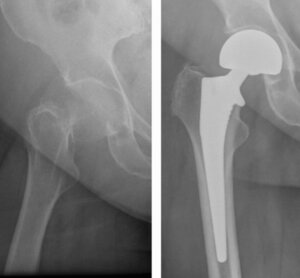

Registry data corroborate these findings with the Swedish registry PROMs consistently reporting higher satisfaction and functional scores after THA compared with HA.20 Conversion of HA to THA for acetabular erosion restores function but carries higher revision and complication rates than primary THA.75 (Figure 3)

Smith et al. directly compared outcomes between THA performed for FNFs and elective THA for OA, demonstrating that despite older age and greater frailty fracture patients can achieve nearly equivalent one-year functional results.18 In their 864-patient series, one-year Harris Hip Scores were 94.9 for FNF-THA versus 96.6 for OA-THA (p < 0.001), reinforcing the capacity of current arthroplasty practices to achieve near-normal function even in higher-risk fracture populations.

DM constructs further improve functional recovery by reducing dislocation risk, thereby avoiding instability-related revision that negatively impact PROMS.65–67 FJS are consistently higher with DM compared to conventional THA at early follow-up, reflecting greater stability and confidence in mobility.68